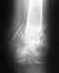

Мне 32 года...рентгенограмма 5 месяцев после перелома...хотелось бы услышать как сделана операция...да и вообще мнение специалиста